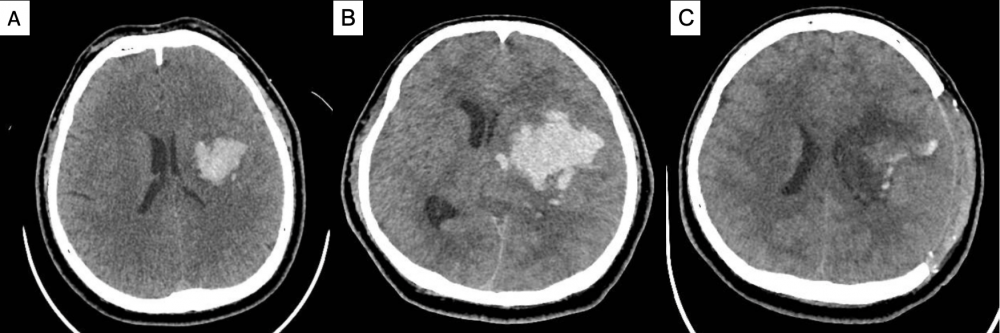

Hình 2. CT scan sọ não của bệnh nhân nam 35 tuổi với xuất huyết trong não vùng đồi thị bao trái trong giờ thứ 1 sau đột quỵ (A), tiến triển xuất huyết giờ thứ 3 gây tăng áp lực nội sọ, đẩy lệch đường giữa sang phải (B). Bệnh nhân được tiến hành phẫu thuật mở sọ giải áp, lấy máu tụ tiêu chuẩn (C).